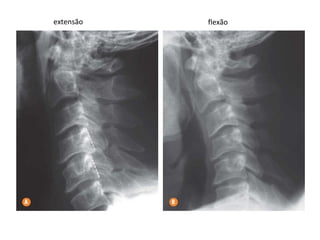

INCIDÊNCIA COLUNA CERVICAL

ESTRUTURAS MAIS DEMONSTRADAS: Estudo funcional para demonstrar os

movimentos das vértebras cervicais.

extensão flexão